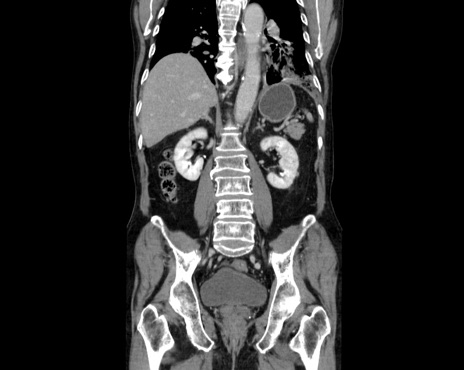

症例26(冠状断像)

【症例】80歳代男性

【主訴】嘔吐

【現病歴】昨晩2回嘔吐あり、今朝になっても嘔吐あり。来院。

【既往歴】胃潰瘍

【身体所見】意識清明、BT 37.6℃、BP 166/95mmHg、HR 100bpm、SpO2 97%、腹部:平坦・軟、腸蠕動音聴取良好、圧痛なし。

【データ】WBC 21900、CRP 1.4